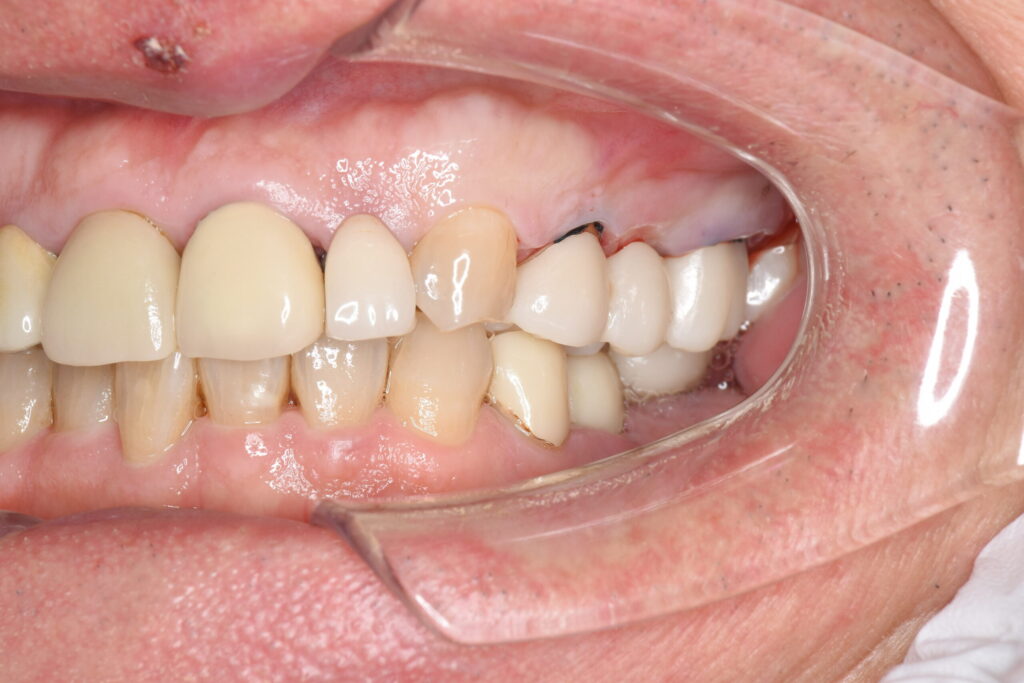

患者様は、奥歯4本の銀歯の色を変えたくて来院されました。虫歯の再発予防もしたいのでセラミックでの治療を希望されており、メリットデメリットと、起こりうるリスクについて説明の後、治療を開始しました。

ブリッジは欠損部分の両隣の歯を支えにするため、土台の歯には常に大きな負担がかかります。銀歯の場合、経年劣化による変形やセメントの流出によって、土台との間に隙間が生じやすく、そこから二次虫歯が進行して土台ごと失うリスクがありました。対してセラミックは変質せず、歯と強固に接着するため、細菌の侵入を許さず土台の歯をしっかり守り抜きます。

さらに、金属アレルギーの心配がなく、歯ぐきの黒ずみ(メタルタトゥー)も解消されるため、健康で明るい口元を長期的に維持することが可能になります。

| 銀歯を除去し、ジルコニアブリッジにて補綴処置を行なった。 |